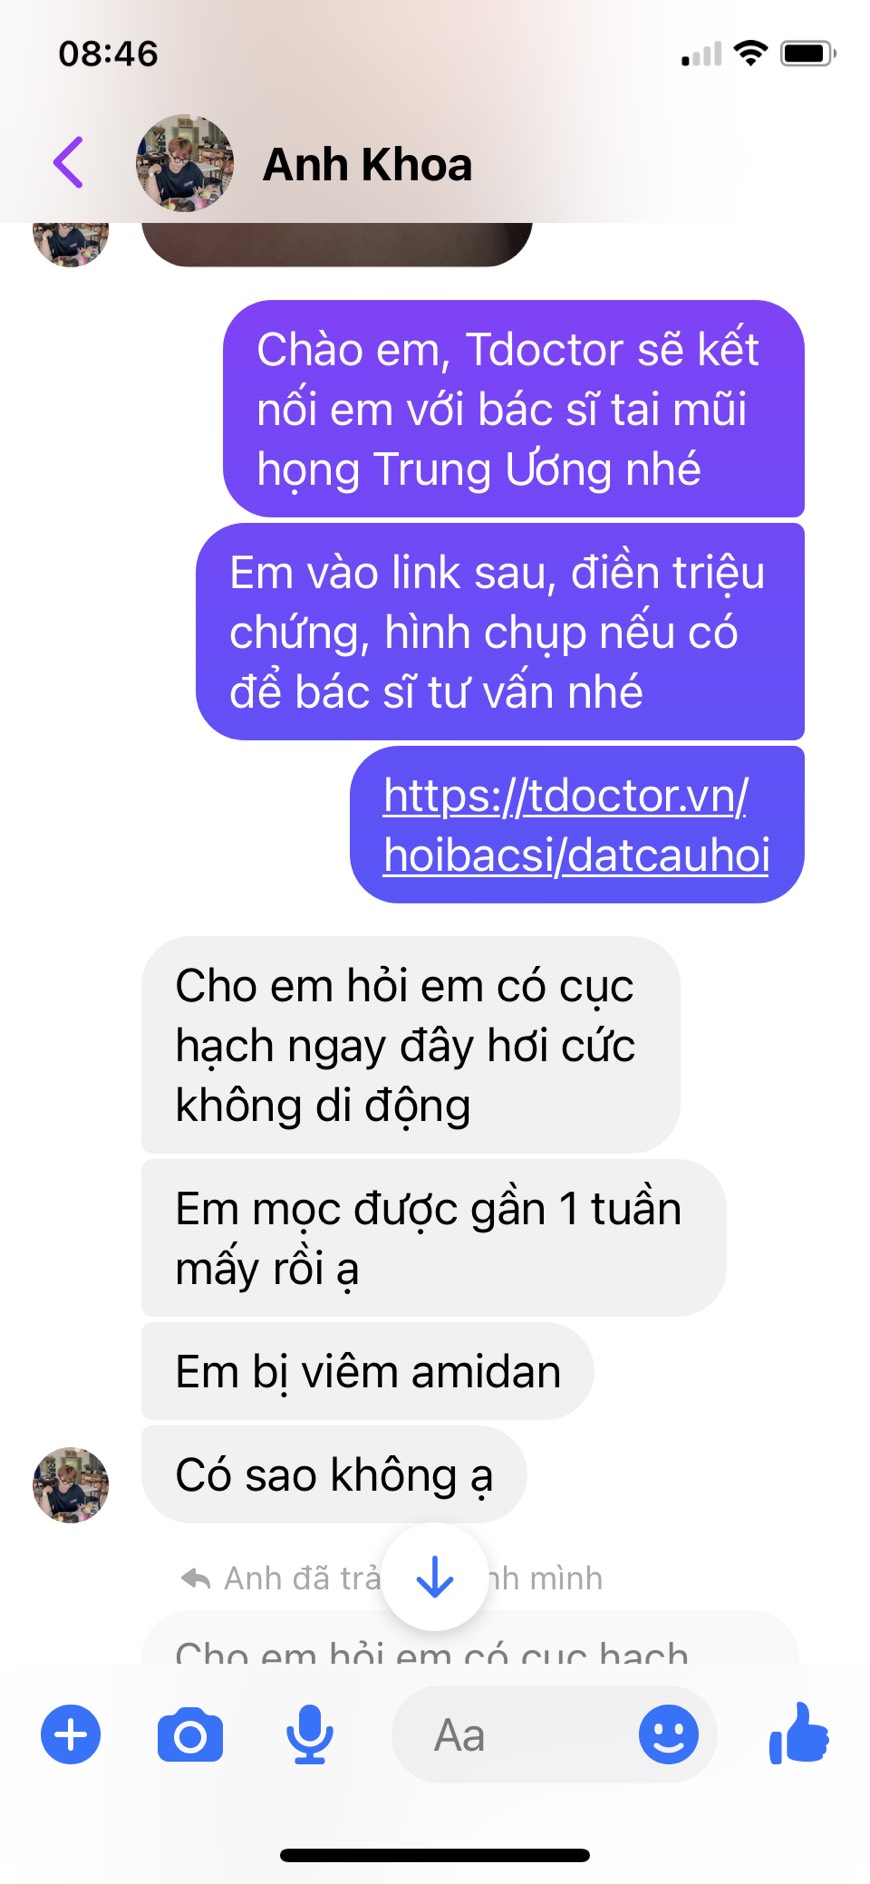

Hỏi đáp trực tiếp với bác sĩ uy tín

Đặt câu hỏi miễn phí

Đặt câu hỏi miễn phí

Hơn 1000 Bác sĩ đang sẵn sàng giúp đỡ bạn